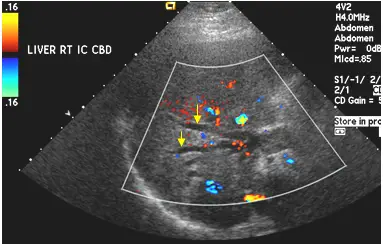

彩色超音波掃描如附圖,箭號所指處為何?

本題考察彩色超音波掃描(color Doppler ultrasound)在鑑別肝內管狀結構方面的應用,重點在於判斷肝內膽道擴張(intrahepatic biliary dilatation)的特徵性表現,並與門靜脈(portal vein)、肝靜脈(hepatic vein)及肝內動脈(hepatic artery)在彩色都卜勒(color Doppler)上的差異。

此彩色超音波影像標示「LIVER RT IC CBD」,顯示肝臟右葉區域。影像中可見:

- 箭號所指:黃色箭號指向肝內一組管狀無回音(anechoic)結構,這些結構呈現平行排列,緊鄰門靜脈走行,形成所謂的「平行管徵象」(parallel channel sign / double barrel shotgun sign)。

- 關鍵彩色都卜勒特徵:箭號所指的管腔內無彩色血流訊號(呈黑色/無色),而鄰近的門靜脈及小動脈則顯示有彩色血流訊號(紅色/藍色)。

- 影像右側可見少量彩色血流訊號,代表附近的血管結構(門靜脈分枝及肝動脈)有正常血流。

- 無彩色訊號的平行管腔結構即為擴張的肝內膽管,與門靜脈分枝平行走行,此為肝內膽道擴張的典型超音波表現。